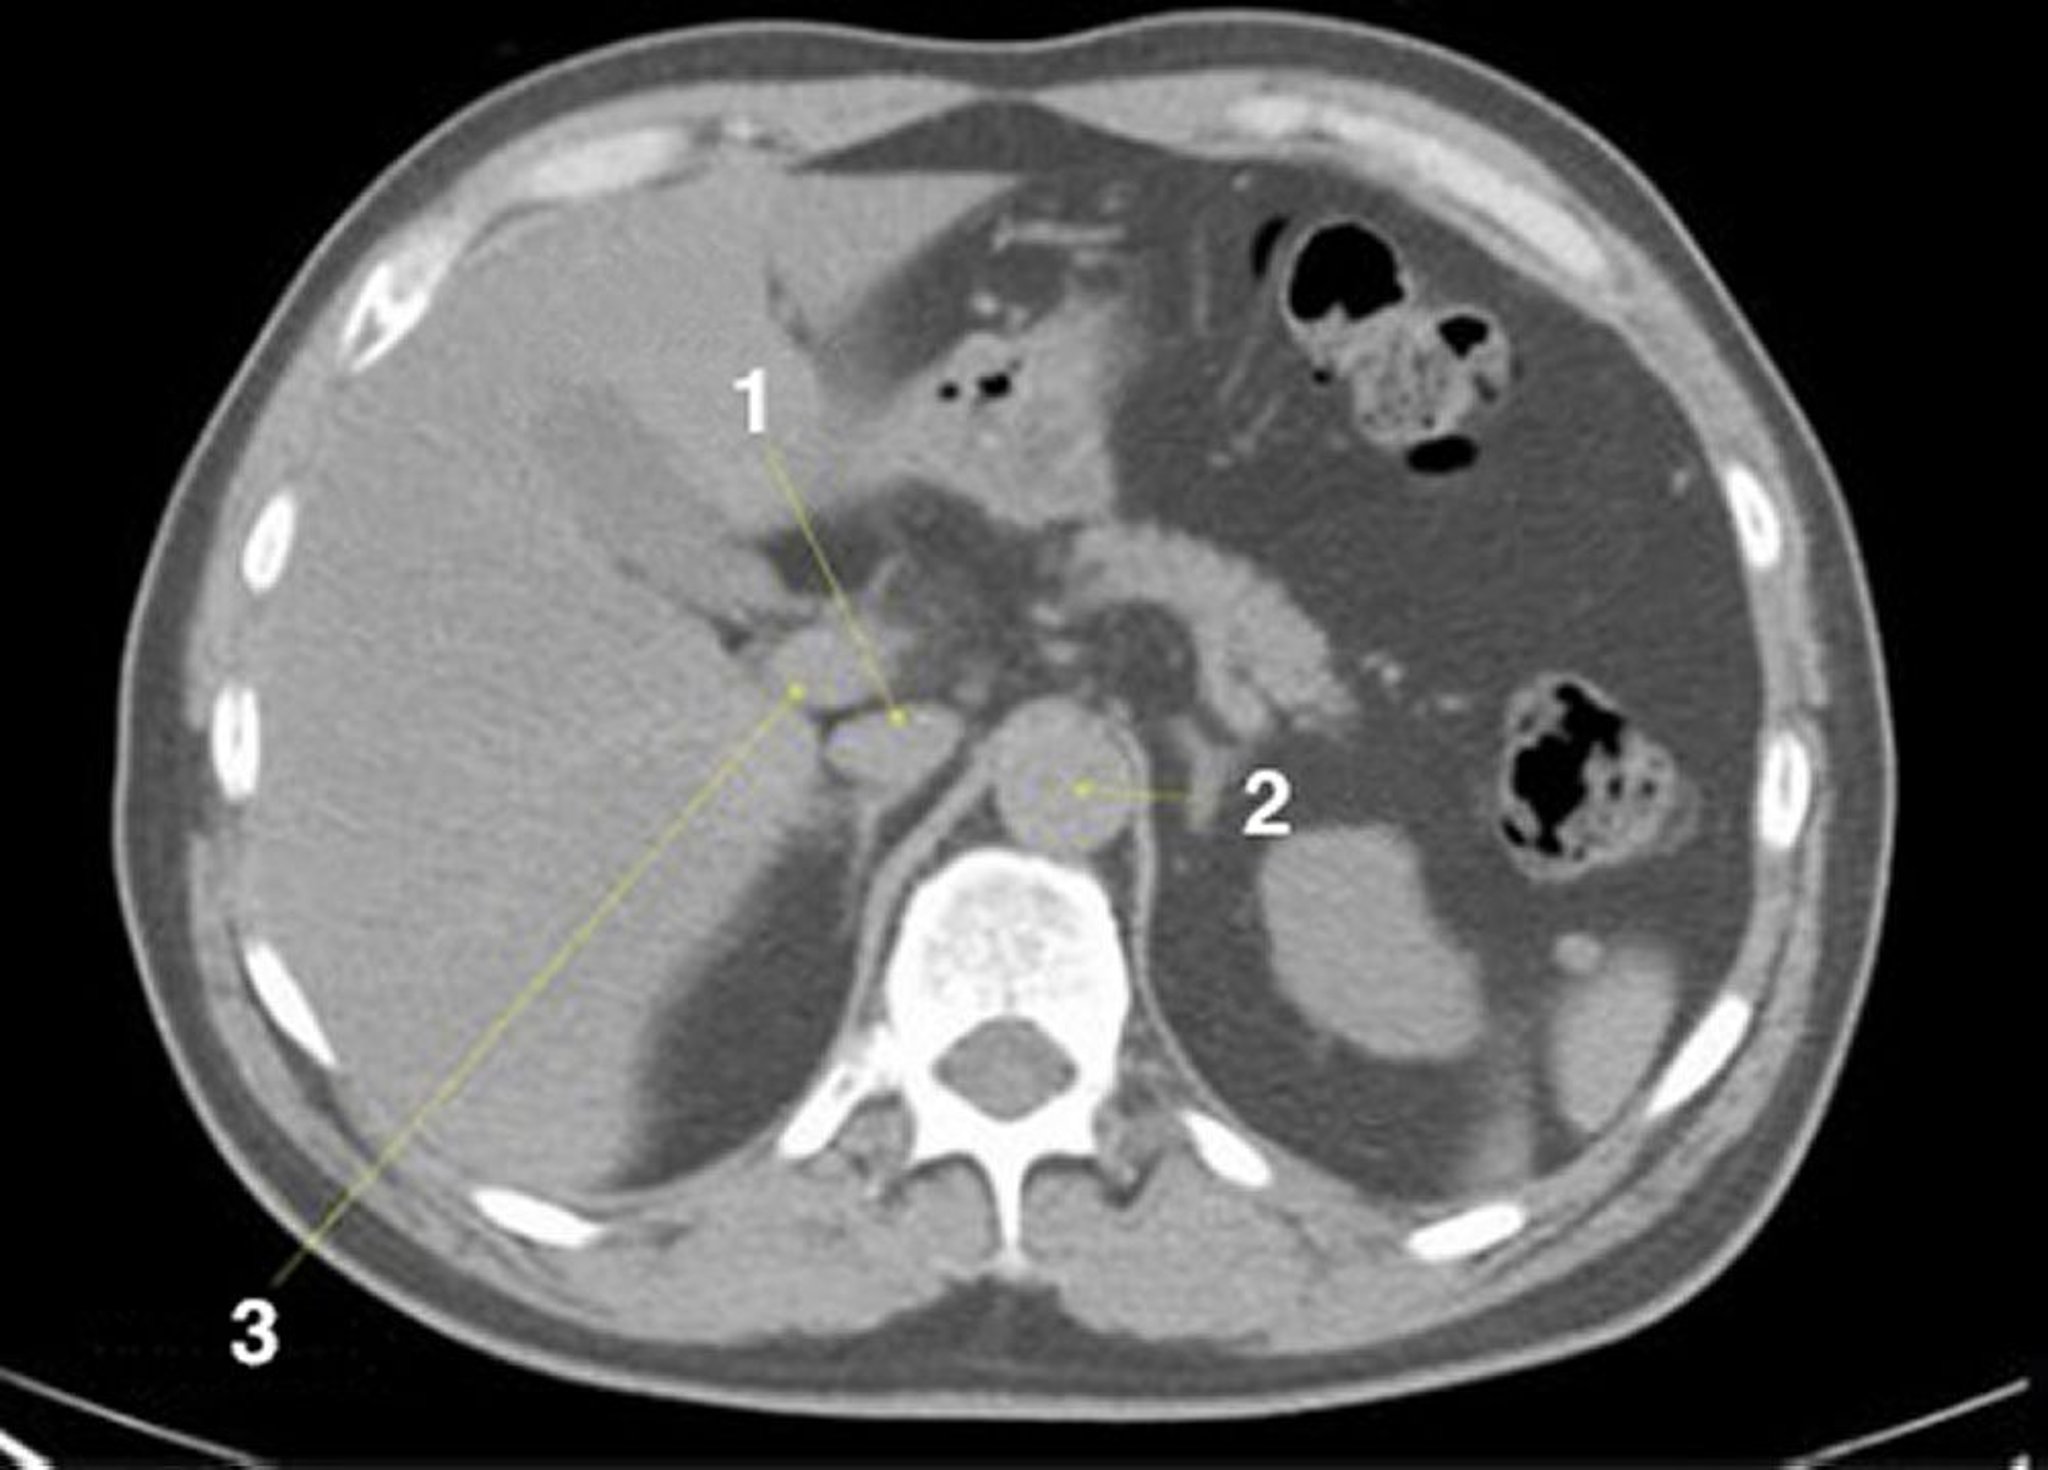

CT-Scan von Abdomen und Becken mit normaler Anatomie ohne Kontrastmittel (Folie 6)

1 = V. cava inferior; 2 = Aorta; 3 = Pfortader.